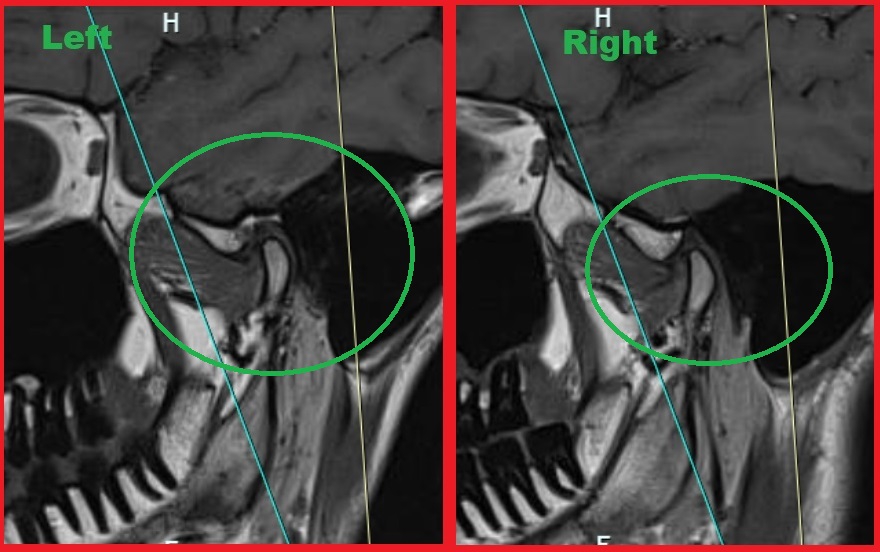

Я в разрезе у себя МРТ заметил что с одной стороны мыщелок кости какой-то более острый, стертый будто. Почему мне никто об этом не сказал, хотя и КТ делал и репорт МРТ получал, никто об этом там даже не написал. Я что-то не понимаю?

Я ещё несколько снимков в разрезе склеил и загрузил и чатгпт 4. И вот что он сказал. Пикрелейтед 1 и 2 снимки с закрытым и открытым ртом. Пикрелейтед 3 анализ чатгпт на основе снимка 1 (2ой ещё не загрузил ему потому что лимит на сегодня загрузок). Теперь вопрос. Если я чат ГПТ видит воспаление, неровность, то почему мой радиологист нихуя этого не увидел?

>>1559645

Это всё ОП